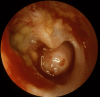

Is chronic suppurative otitis media a neglected tropical disease?